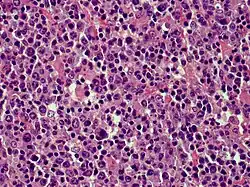

| Cutaneous diffuse large B-cell lymphoma | |

Cutaneous B-cell lymphomas (CBCL), more recently termed Primary cutaneous B-cell lymphomas and lymphoproliferative disorders (PCBCLPD), are a group of disorders that typically present as skin lesions consisting of proliferating B-cells. B-cells are a type of lymphocyte involved in regulating immune responses. (The "primary" used to designate cutaneous lymphomas indicates that the lymphoma was first diagnosed as limited to the skin and there was no evidence of spread to extracutaneous tissues for 6 months after the diagnosis was first made.[1]) Since its original definition in 1997, CBCL has been considered to have a varying number of subtypes by the European Organisation for Research and Treatment of Cancer, i.e., EORTC, and World Health Organization, i.e., WHO.[2] The latest revised classification of CBCL, which was published by EORTC in 2022, lists the following three main subtypes of CBCL (now termed PCBCLPD):[3]